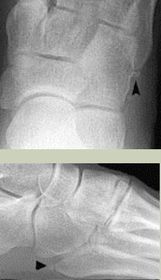

What is this? What is shown by A and B? | STJ coalition A = talar neck spurring B = Halo or 'C' sign |